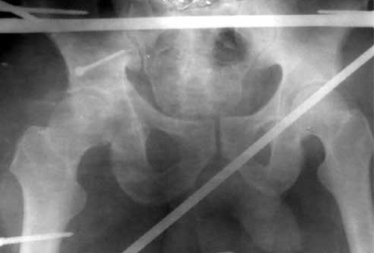

Для ранней активизации больного операция заканчивается установкой аппарата внешней фиксации. Аппарат позволяет гарантированно стабилизировать тазобедренный сустав с заданной или регулируемой разгрузкой, что создает условия не только для срастания перелома, но и для расправления или восполнения участков импрессии или компрессии с восстановлением структуры субхондрального слоя (рис. 2, 3).

Обзорная рентгенограмма таза. Состояние после открытой репозиции и фиксации верхнего отдела заднего края вертлужной впадины винтом. Стабилизация и разгрузка тазобедренного сустава в аппарате внешней фиксации